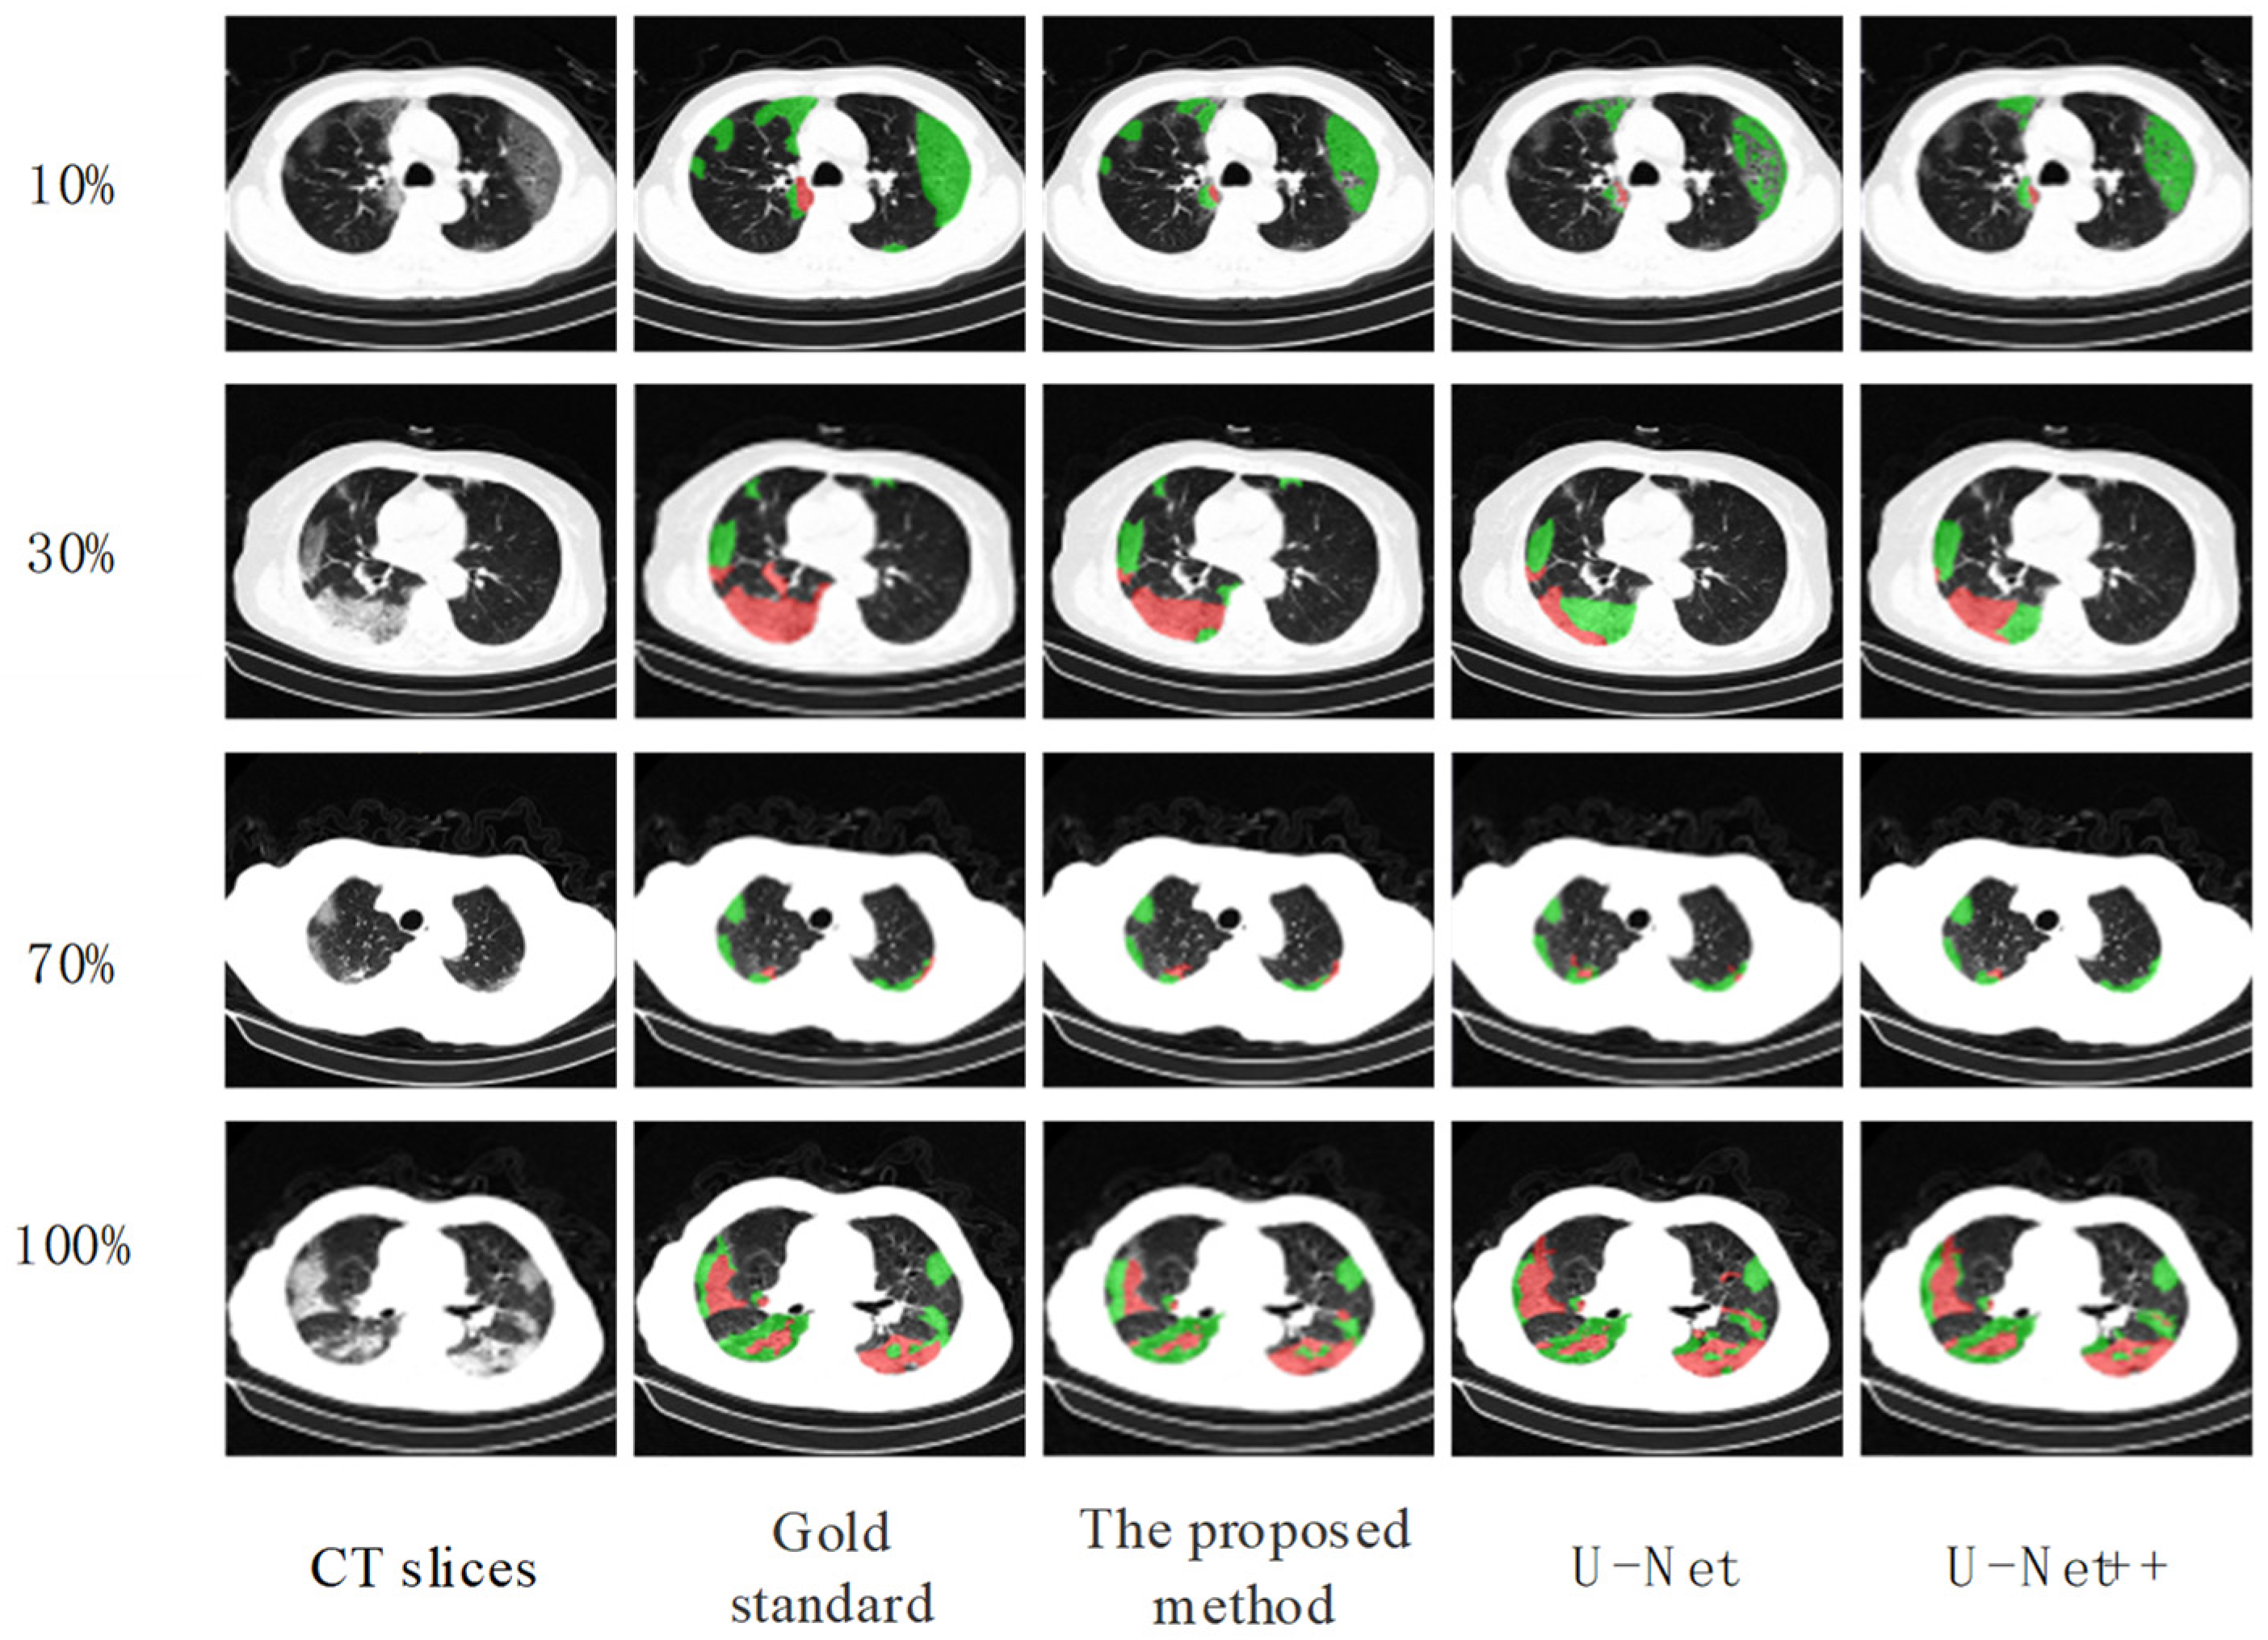

4.5. Segmentation Results of COVID-19 Lesions

| Labels | Method | Dice % |

|---|---|---|

| 10% | Ours | 74.94 |

| U-Net | 58.06 | |

| U-Net++ | 57.21 | |

| 30% | Ours | 78.32 |

| U-Net | 66.44 | |

| U-Net++ | 66.27 | |

| 70% | Ours | 82.11 |

| U-Net | 74.09 | |

| U-Net++ | 76.32 | |

| 100% | Ours | 84.91 |

| U-Net | 79.33 | |

| U-Net++ | 81.16 |